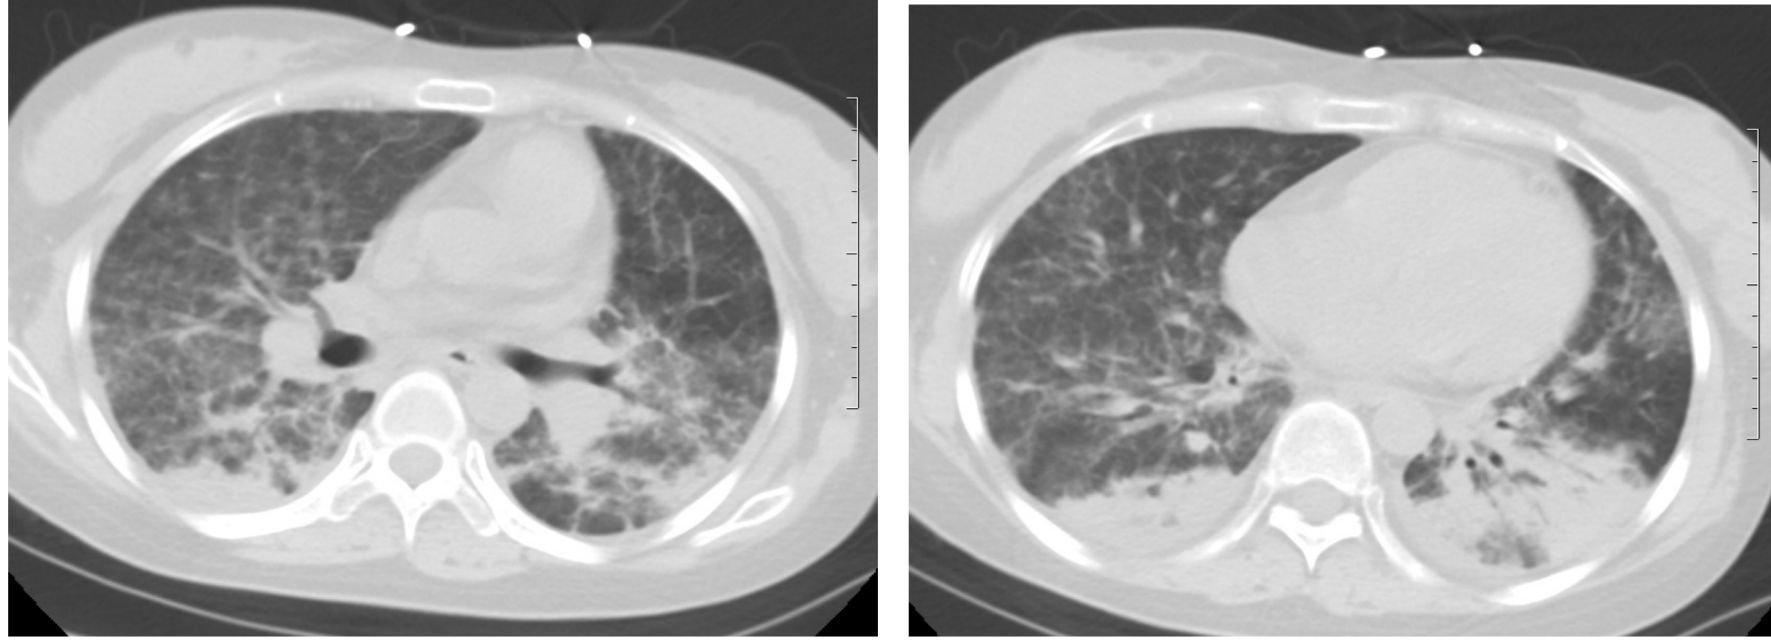

患者,女,24岁,主因“发热、干咳20余天”入院。外院抗生素治疗效果差。既往肾病综合征,口服激素。查体:T 38 ℃、P 105次/min,RR 20次/min,BP 102/73 mmHg(1 mmHg=0.133 kPa),双肺未闻及啰音。辅助检查:WBC 1.52× 109 L-1、NE 78.3%;CRP 71 mg/L;ALT 248 U/L、AST 118 U/L;动脉血气(未吸氧):pH 7.44,PaCO2 34 mmHg,PaO2 69 mmHg;胸部平片未见异常。入院后美罗培南治疗3 d,未见好转,呼吸困难进行性加重,I型呼吸衰竭。第3日胸部CT提示双肺间质弥漫渗出,部分实变(图 1),病原不明确,调整抗感染方案:美罗培南、莫西沙星、磺胺、卡泊芬净、更昔洛韦250 mg/12 h、甲强龙40 mg/d、丙种球蛋白。第6日症状明显好转,复查胸部CT较前明显吸收(图 2),此时回报PCT、血培养、G试验、GM试验、呼吸道病原菌培养均阴性;CD4、CD8及CD4/CD8显著下降;肺泡灌洗液CMV-DNA 9.4×105 拷贝/mL,血清CMV-DNA 4.35×104 拷贝/mL,考虑巨细胞病毒肺炎诊断明确,维持更昔洛韦、甲强龙治疗3周,1月后胸部CT示渗出及实变完全吸收(如图 3)。

图 3 1月后胸部CT